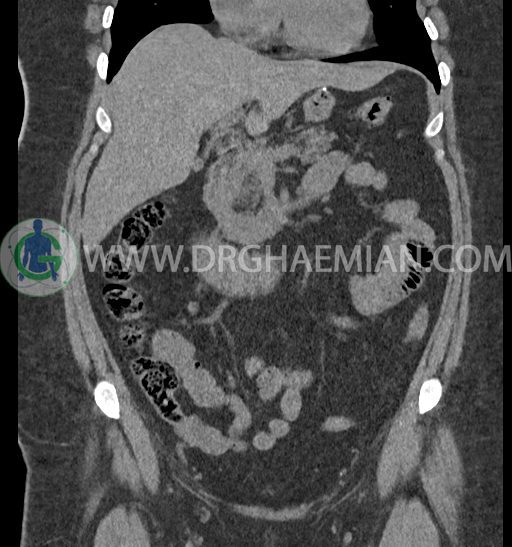

سی تی اسکن شکم و لگن با استفاده از اشعات ایکس تصاویر عرضی از ناحیه شکم و لگن ایجاد میکند. در این کیس کلیه نعل اسبی و سنگ کلیه مشاهده می شود.

در سی تی اسکن اسپیرال شکم و لگن بدون کنتراست (مولتی دیدکتور 16 با مقاطع ظریف و بازسازی های ساژیتال و کرونال) :

-horseshoe kidney

-حداقل سه سنگ 5mm در کلیه راست و یک سنگ 3mm در کلیه چپ بدون شواهدی از هیدرونفروز

-شواهد جراحی اسلیو قبلی در Body و فوندوس معده

-آپاندیس نرمال بصورت رتروسکال

مشهود است.